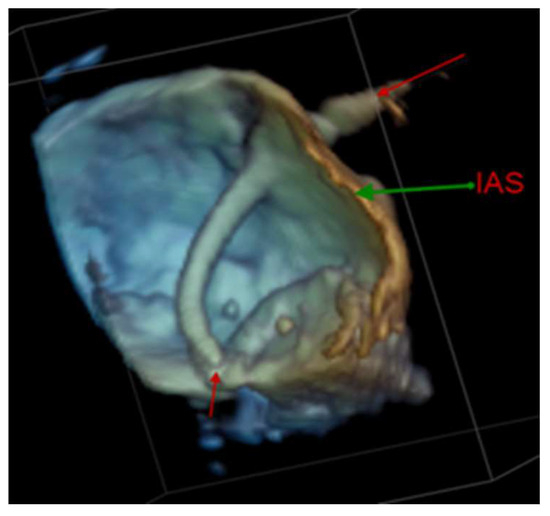

4.2.1. Transseptal Puncture

4.2.4. Atrial Septal Defect Occlusion